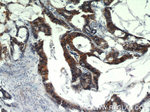

EPCAM Antibody in Immunohistochemistry (Paraffin) (IHC (P))

免疫组化(石蜡) (IHC (P))

1:50-1:500